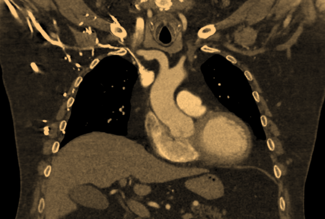

Percutaneous left atrial appendage occlusion (LAAO) with the Watchman device is FDA approved for stroke prevention in patients with nonvalvular atrial fibrillation who have an appropriate indication.